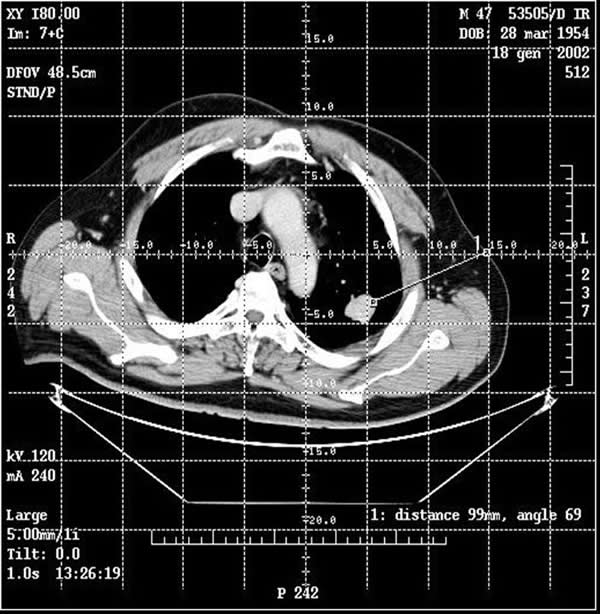

The procedure is performed with the patients under conscious sedation (Ketorolac 0.5-0.8 mg/kg, propofol 1-2 mg/kg/h, and remifentanil 0.1mg/kg/min) and local anesthesia (subcutaneous 1% xylocaine). Vital signs are continuously non-invasively monitored. CT guidance is employed in most of the cases; it is usually enhanced by the administration of contrast material before and after coagulation to obtain information about the real effectiveness of the procedure (Figure 3). In a selected group of patients with the tumour in contact with the thoracic wall, it is possible to work under ultrasound guidance (Video 2). The needle-electrode is inserted through an intercostal space after administration of local anaesthesia (Video 3). The correct placement is confirmed by CT (Figure 4) or ultrasound (Video 4) before applying the radiofrequency energy. The target temperature of ablation is 90°C. It is maintained for a time ranging from 15 to 27 minutes according to the size of the tumor; this variable also determines the gradual deployment of the electrodes, starting from 2 cm and then 1 cm for each step. When technically feasible, the ablation zone should include the whole lesion and one cm of the surrounding lung parenchyma.

Figure 3. By CT guidance it is possible to establish the site, depth, and angle for insertion of the needle electrode.